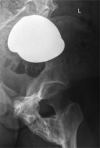

Fibrodysplasia ossificans progressiva (FOP) is a rare genetic disorder and the most disabling condition of heterotopic (extraskeletal) ossification in humans. Extraskeletal bone formation associated with inflammation preceding the osseous conversion usually begins in the first decade, predominantly in the head, neck, and shoulders. All patients have malformed great toes. Most patients have a spontaneous mutation of the ACVR1 gene. We report a 17-year-old girl with malformed great toes who had her first episode of heterotopic ossification and impaired mobility of the left hip at the age of 13 years. No inflammatory fibroproliferative masses preceded the onset of heterotopic ossification. Radiographic studies demonstrated myositis ossificans, but failure to associate the great toe malformation with heterotopic ossification led to a failure to diagnose FOP. She underwent repeated and unnecessary operative procedures to remove a recurrent lesion. FOP was finally suspected when the great toe malformation was correlated with the trauma-induced heterotopic ossification. Genetic analysis confirmed the presence of the classic FOP mutation (ACVR1 c.617G>A; R206H). This case highlights the importance of examining the great toes in anyone with heterotopic ossification. The association of malformations of the great toe with heterotopic ossification in all cases of classic FOP will lead to prompt clinical diagnosis and the prevention of iatrogenic harm.